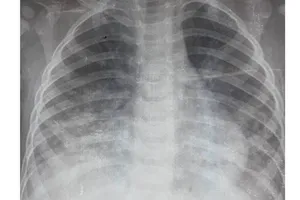

Trẻ 17 tháng tuổi viêm phổi nặng do uống dầu hỏa

Y tế - Sức khỏe

21/07/2017 17:05